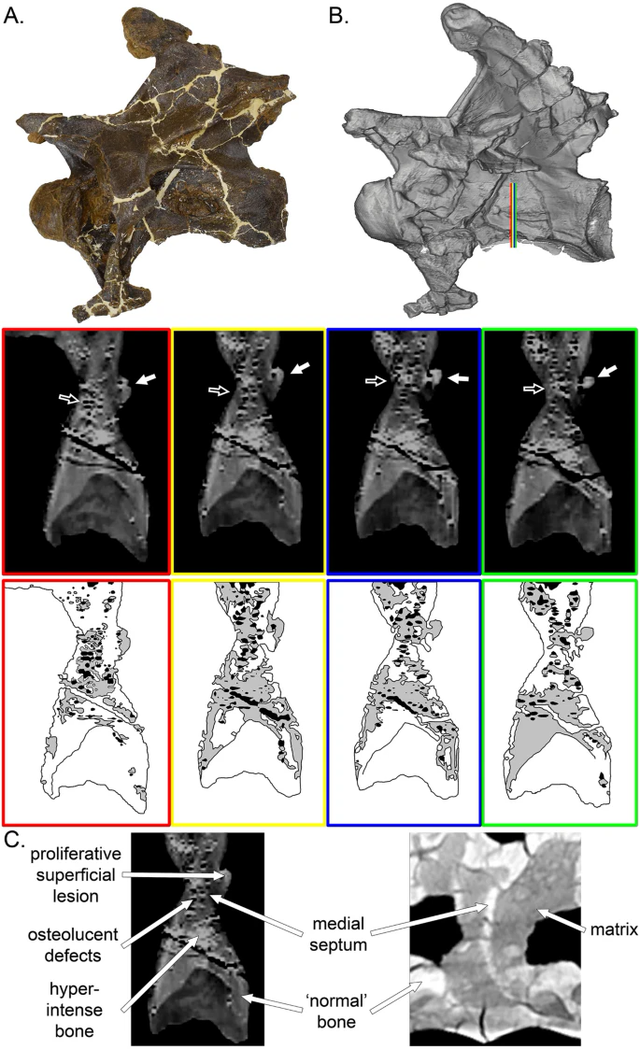

Các đốt sống cổ của MOR 7029 có biểu hiện biến dạng âm học rõ ràng (bao gồm cắt và nghiền), nhưng có những cấu trúc bất thường. Ở những đốt sống này, sự thay đổi không đối xứng, hình thái, vị trí và kết cấu của những cấu trúc này làm nổi bật nguồn gốc bệnh lý liên quan đến các rìa hóa thạch khí nén. Mặc dù rất khác nhau, những cấu trúc này có bề ngoài dạng nốt sần đa tiêu điểm gây ra một bề mặt rất nhấp nhô và không đồng nhất. Sự tăng sinh của xương khác nhau về kích thước và mức độ.

Trong quá trình tìm hiểu, nhóm nghiên cứu phát hiện ra rằng ba chiếc xương ở cổ của nó có một di tật và một số cục u. Dựa trên vị trí của ba chiếc xương, các nhà cổ sinh vật học suy đoán rằng các cục u được hình thành sau khi các túi khí của Dolly bị nhiễm trùng rồi lan dần đến xương.

Đồng thời các phân tích chuyên sâu cũng suy đoán rằng sự thình thành của những cục u này có thể là do nhiễm trùng nấm có tên Aspergillus. Những suy đoán này được dựa trên các triệu chứng tương tự thường xuyên được quan sát thấy ở các loài chim và bò sát hiện đại. Aspergillus là một bệnh hô hấp phổ biến, ảnh hưởng đến các loài chim và bò sát, đôi khi gây nhiễm trùng và gâu biến dạng xương của những động vật này, nặng hơn thì có thể dẫn đến tử vong.

Theo Cary Woodruff, Giám đốc Cổ sinh vật học tại Bảo tàng Great Plains Dinosaur ở Malta, Montana, cũng là tác giả chính của nghiên cứu, con vật đã chết khi được 15-20 tuổi. Những con khủng long sauropod thường đến tuổi trưởng thành ở cuối độ tuổi 20. Sauropod và khủng long ăn thịt được gọi là theropod, một nhóm bao gồm các loài chim, sở hữu các đường hô hấp phức tạp hơn động vật có vú. Ngoài phổi, chúng còn có các túi khí mỏng, giống như quả bóng kết nối với khoang cơ thể và nhiều xương. Ở Dolly, xương phát triển bất thường ở đoạn nối giữa mô hô hấp và xương ở ba đốt sống, bằng chứng cho thấy nhiễm trùng đã lan rộng từ phổi.